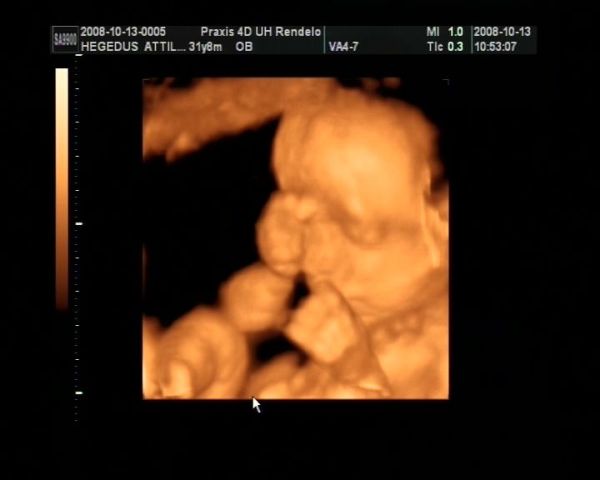

Tegnap voltunk 4d-s uh-on :) Hatalmas élmény volt. Viszont lesz egy komoly beszélgetésem a kisfiammal :) El kell magyaráznom neki, hogy a lányokra még nézni is csak szépen szabad, homlokon rugdosni őket pedig abszolút tilos. Még nézni is fájt, hogy miket művelt Eszterrel... Konkrétan az arcába ült, vagy a combját nyomta a nyakához, egyszer meg sarokkal homlokon rúgta. Mekkora harcok mehetnek bent... Eszterkém pofijáról nem is készült sok jó kép, mindegyiken belelóg Ádám feneke. Egyébként csodaszép két kölök, és makkegészségesek. Most épp fejjel lefelé voltak mindketten, de ahogy elnéztem őket ez egyelőre még kb 10 percenként változik :) És akkor a képek:

Ádámbátyám:

Kép

És Eszter: